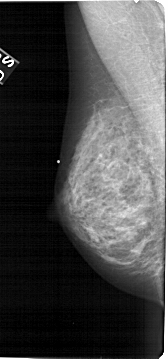

A_1472_1.RIGHT_CC

RIGHT_CC LINES 5086 PIXELS_PER_LINE 2356 BITS_PER_PIXEL 12 RESOLUTION 43.5 OVERLAY